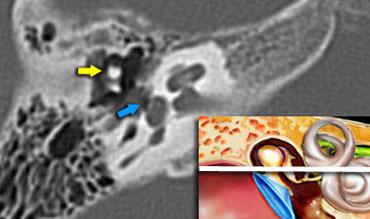

Cán xương búa (mũi tên vàng) được nối với màng nhĩ.

Đầu xương búa được thấy nằm phía trước đầu xương đe (mũi tên vàng).

Scutum (mũi tên vàng). Đầu xương búa (mũi tên cam) được thấy nằm phía trong so với xương đe (mũi tên xanh lá)

Scutum (mũi tên vàng) là một gai xương nhọn được tạo thành bởi thành ngoài của hòm nhĩ và thành trên của ống tai ngoài.

Đây thường là cấu trúc xương đầu tiên bị ăn mòn do cholesteatoma, được hình thành bởi sự co kéo vào trong của màng Shrapnell (pars flaccida) của màng nhĩ vào thượng nhĩ.